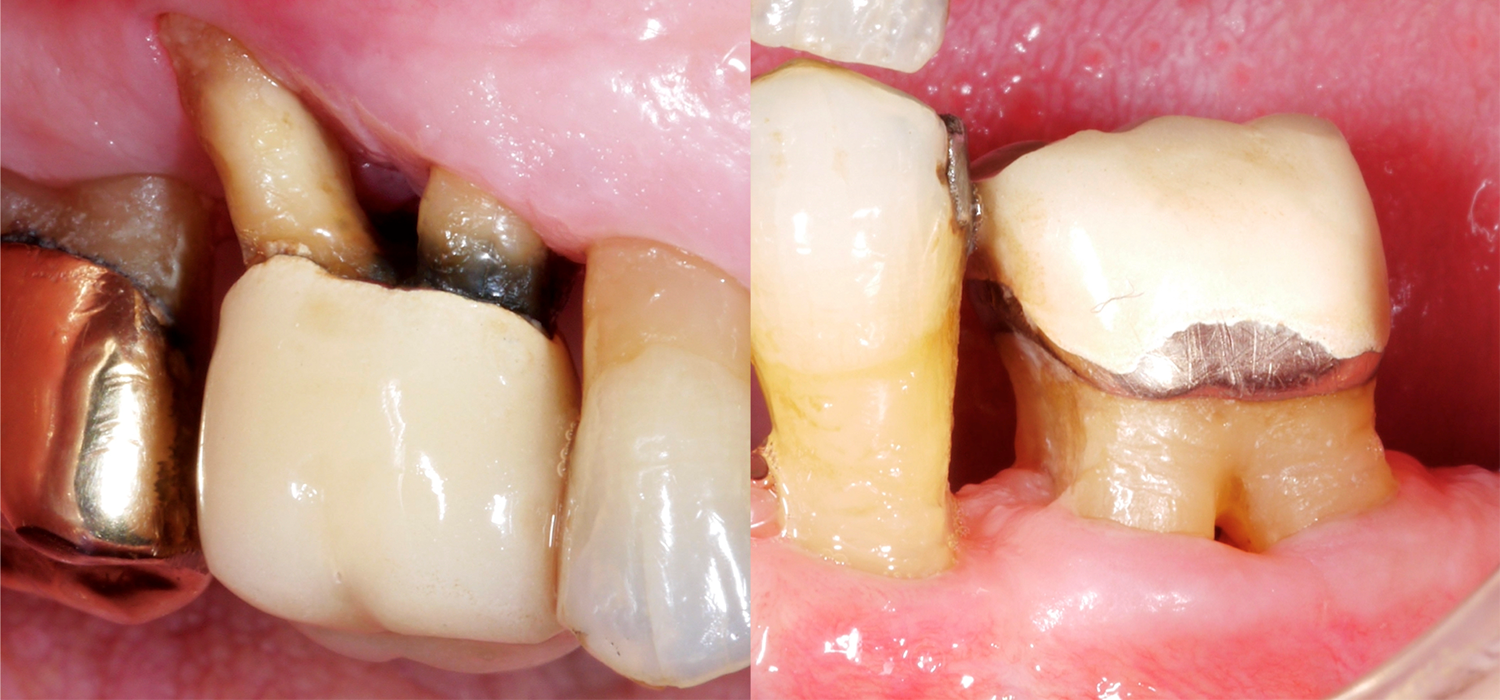

Wenn man nun an die Zähne denkt, dann sind natürlich mehrwurzelige Zähne oft viel schwieriger zu therapieren, im Speziellen, wenn sie einen Furkationsbefall aufweisen. Warum ist der Furkationsbereich so anspruchsvoll? Der Zugang für die mechanische Reinigung der Wurzeloberfläche ist im Vergleich zu einwurzeligen Zähnen viel schwieriger, der Furkationseingang kann oft sehr klein/schmal sein, und zusätzlich kann es noch anatomische Besonderheiten, wie beispielsweise Schmelzprojektionen, geben.